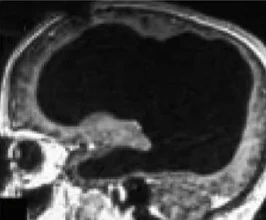

در نمونه ای نادر، یک فرد با از دست دادن حدود ۹۰ درصد از مغز خود همچنان از هوشیاری کامل برخودار است. این اتفاق باعث شده که دانشمندان بار دیگر بر نظریههای خود و تعریف هوشیاری از نظر بیولوژیکی بازنگری کنند. با زومیت همراه باشید تا در مورد این نمونهی پزشکی بیشتر بحث کنیم.